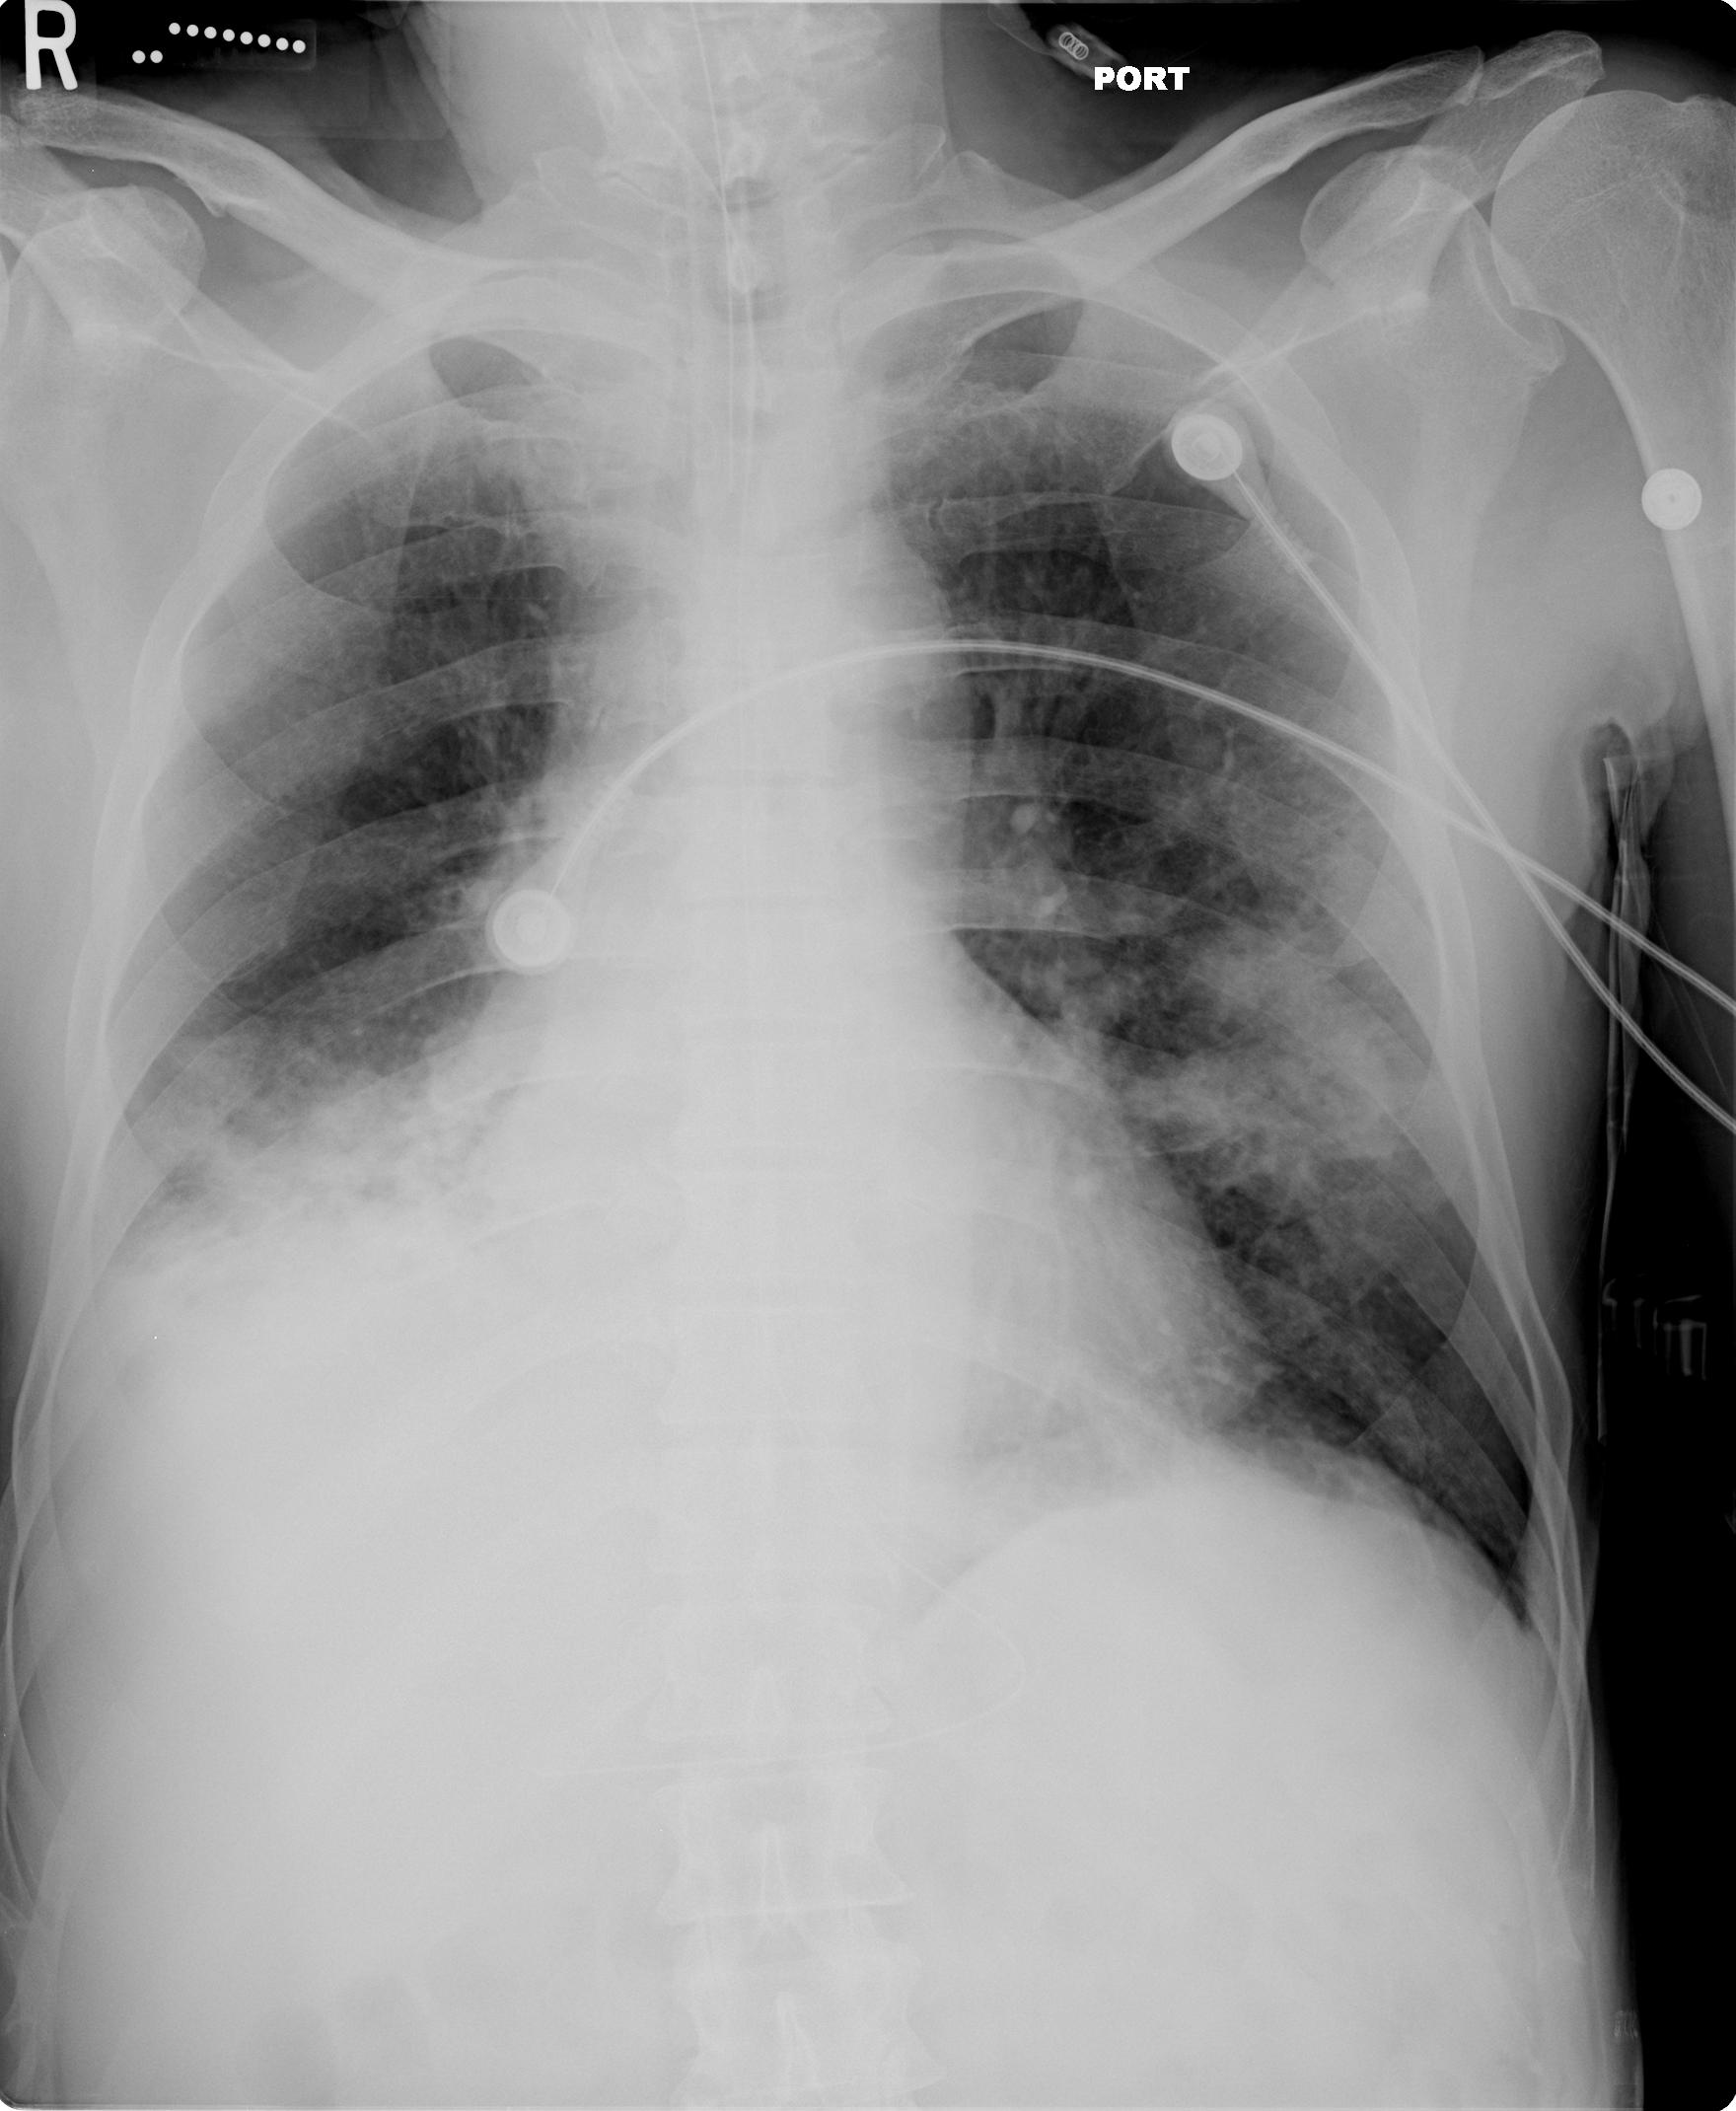

History

A 67-year-old man who was recently diagnosed with pulmonary tuberculosis and treated with four-drug antituberculous directly observed therapy for the last month presented to the emergency department with hemoptysis. The patient stated he had small amounts of blood-streaked sputum for the past 2 weeks, but noted that immediately prior to coming to the emergency department he had coughed up approximately “a cup” of bright red blood. While still in the emergency department, he had a witnessed episode of large volume hemoptysis, estimated to be greater than 250 cc of fresh blood.

Figures